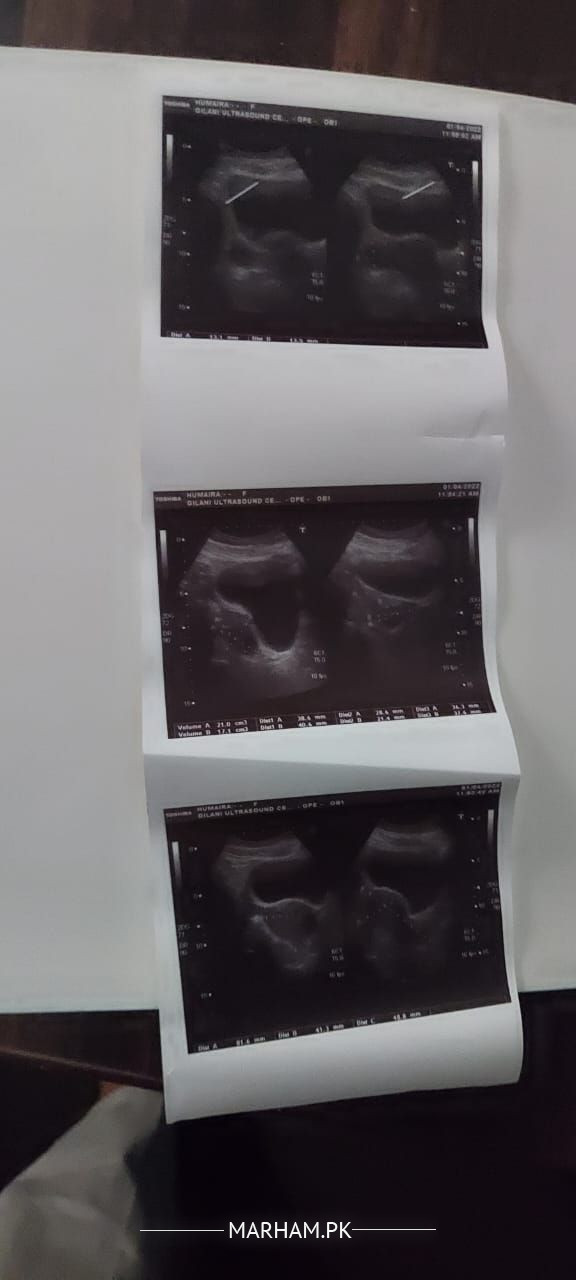

Dr mjy periods k doran bhot sakht pain hota ha. or ma conceived b ni kr pa rahe mere report plz check kr k bta dain k kya msla ha

You have polycystic disease, it needs extensive treatment . Visit any doctor in clinic